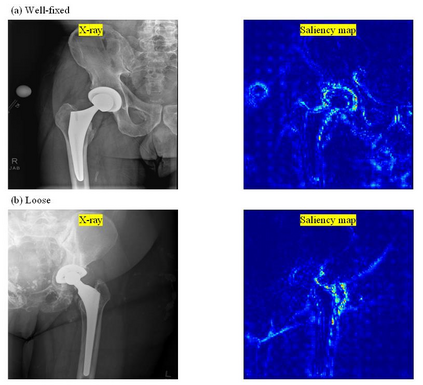

Plain radiography is widely used to detect mechanical loosening of total hip replacement (THR) implants. Currently, radiographs are assessed manually by medical professionals, which may be prone to poor inter and intra observer reliability and low accuracy. Furthermore, manual detection of mechanical loosening of THR implants requires experienced clinicians who might not always be readily available, potentially resulting in delayed diagnosis. In this study, we present a novel, fully automatic and interpretable approach to detect mechanical loosening of THR implants from plain radiographs using deep convolutional neural network (CNN). We trained a CNN on 40 patients anteroposterior hip x rays using five fold cross validation and compared its performance with a high volume board certified orthopaedic surgeon (AFC). To increase the confidence in the machine outcome, we also implemented saliency maps to visualize where the CNN looked at to make a diagnosis. CNN outperformed the orthopaedic surgeon in diagnosing mechanical loosening of THR implants achieving significantly higher sensitively (0.94) than the orthopaedic surgeon (0.53) with the same specificity (0.96). The saliency maps showed that the CNN looked at clinically relevant features to make a diagnosis. Such CNNs can be used for automatic radiologic assessment of mechanical loosening of THR implants to supplement the practitioners decision making process, increasing their diagnostic accuracy, and freeing them to engage in more patient centric care.